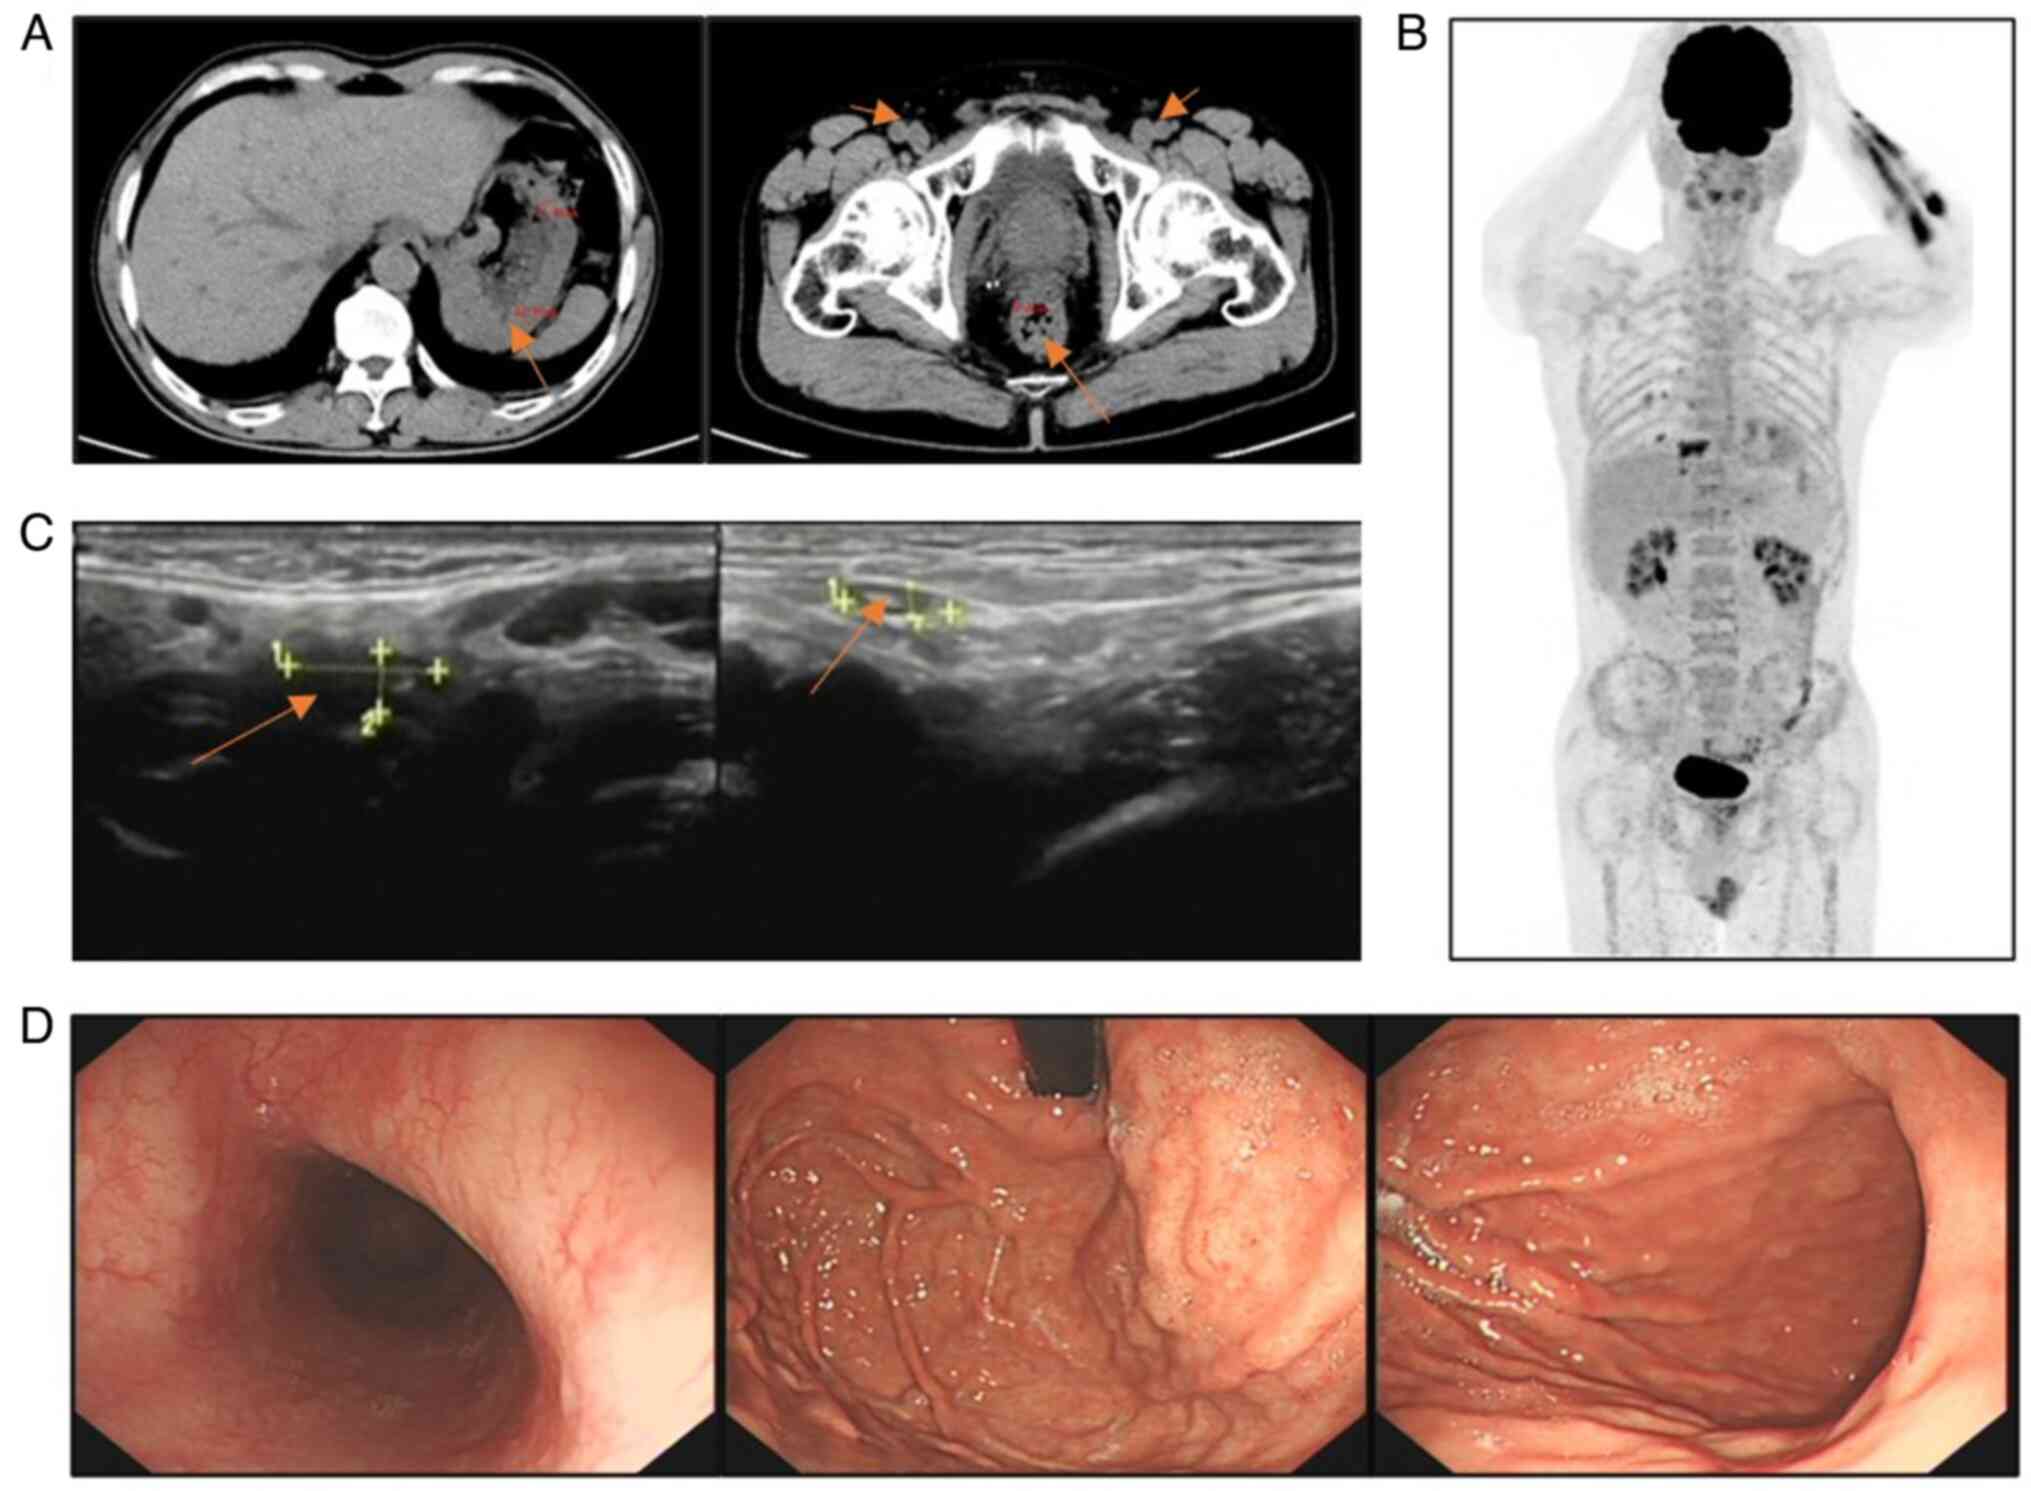

At admission, the body temperature of the patient was 36.4°C, the heart rate was 80 bpm and the blood pressure was 134/80 mmHg. Physical examination revealed mild tenderness of the upper abdomen and superficial lymph node enlargement in the neck, subclavian region and groin. Based on the clinical symptoms alone, the patient could easily be diagnosed with chronic gastritis. CT (Fig. 1A) showed multiple thickenings of the gastric and intestinal walls and numerous enlarged lymph nodes throughout the body. Superficial lymph node ultrasonography (Fig. 1B) revealed enlarged lymph nodes in the bilateral neck, upper and lower clavicle areas, armpits, groin and abdominal cavity. Gastroscopy (Fig. 1C) showed numerous wide basal and circular polypoid lesions in the entire gastric cavity, duodenal bulb and descending part, with rich vascular networks on the surface and a hard texture. Colonoscopy (Fig. 1D) revealed that the ileocecal valve was swollen and uneven, and the valve opening was not visible. The entire tract was covered with wide basal round or spindle-shaped polypoid lesions with a size of 0.5–1.5 cm. The surfaces of the polypoid lesions were rich in vascular networks, and a portion of the lesions were internally erosive, fragile and prone to bleeding. Other abnormal results included the fecal occult blood test [(+; normal value, (−); Colloidal Gold Method] and albumin level of 29.59 g/l (normal range, 35–55 g/l; Bromocresol Green Method). The white blood cell (WBC) count was 9.82×109/l (normal range, 4.00–10.00×109/l). The quantitative value of lactic dehydrogenase (LDH) was 205.4 U/l (normal range, 100.0–240.0 U/l). Based on the symptoms and examination results of the patient, lymphoma was suspected. Samples were fixed using 10% neutral buffered formalin at room temperature (20–26°C) for 24–48 h. Sections (3-µm thick) were stained with hematoxylin staining solution at room temperature for 1 min. The results (Fig. 2A and C); showed patchy lymphocyte infiltration in the mucosa, with local follicular structures. Fluorescence in situ hybridization (FISH; Fig. 2B) indicated that the lesion was CCND1/IGH (−), and immunohistochemical staining (Fig. 3) indicated that the lesion was CD21 (+), CD20 (+), Ki67 (+; 30%), Bcl-2 (+), Bcl-6 (mild+), CD5 (+), CyclinD1 (+) and SOX-11 (+). Therefore, the patient was diagnosed with MCL stage IV and scheduled to be transferred to the Department of Hematology of Hunan Provincial People's Hospital for chemotherapy. After completing tumor assessment, the patient received rituximab in combination with cyclophosphamide, doxorubicin, vincristine and prednisone chemotherapy (R-CHOP). After two cycles of R-CHOP (Table I), a CT scan (Fig. 4A) showed a marked reduction in lymph nodes in multiple areas and less thickening of the gastrointestinal wall compared with previous scans, but did not demonstrate complete response (CR) because there were still abnormalities. Treatment was changed to rituximab combined with etoposide, oxaliplatin and ifosfamide, with the addition of ibrutinib capsules (Table I). After completion of cycle 6 of the treatment, the patient underwent superficial lymph node ultrasonography, gastroscopy and positron emission tomography (PET)-CT in February 2024. The PET-CT scan (Fig. 4B) showed no significant hypermetabolic lesions in the gastrointestinal wall and the lymph nodes throughout the body. The superficial lymph node ultrasonography (Fig. 4C) did not reveal obvious lymph node enlargement. The gastroscopy (Fig. 4D) indicated that the polypoid lesions in the stomach had virtually disappeared. These results showed that the patient had achieved CR. The patient was followed up every 21 days with the medical record system of the hospital.

Figure 1.

(A) CT imaging demonstrating evident thickening of the gastric wall (arrow point) at multiple locations, thickening of the distal ileum wall and formation of ileocecal intussusception; multiple lymph node enlargements in the left lung hilum, bilateral armpits, retroperitoneum, mesenteric area, pelvic cavity and bilateral inguinal region (arrow point); and thickening of the lower rectal wall (arrow point). (B) Superficial lymph node ultrasonography demonstrating that multiple lymph nodes were markedly enlarged throughout the body. From left to right, the cervical (arrow point, 21×11 mm), supraclavicular (10×5 mm) and inguinal (arrow point, 28×8 mm) lymph nodes are shown. (C) Gastroscopy demonstrating multiple protruding lesions with rich vascular networks on the surface and a hard texture. (D) Colonoscopy showing that the ileocecal valve was swollen and uneven, had multiple protruding lesions, the entire tract was covered with wide basal round or spindle-shaped protrusions, and the surfaces were rich in vascular networks.